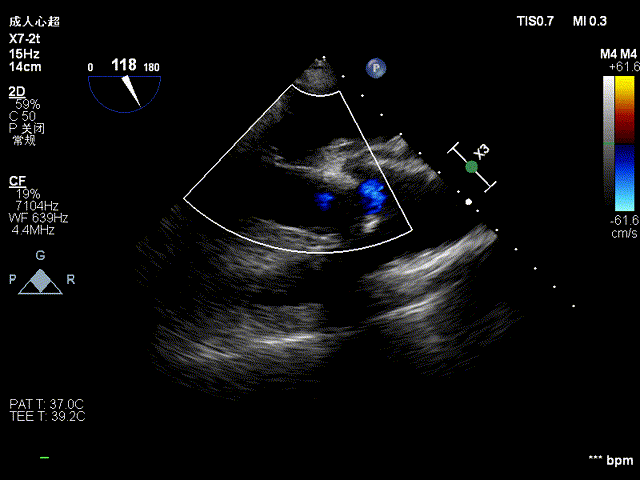

术前术后食道超声对比:

术后

术后心脏彩超检查示:(主动脉瓣生物瓣膜置换+升主动脉成形术后)人工生物主动脉瓣活动良好,左心腔增大,左室射血分数减低,二尖瓣、三尖瓣轻度关闭不全。

主动脉窦部内径4.05cm,主动脉示成形术后回声,壁活动尚可,主动脉瓣示生物瓣结构回声,前向血流速度2.1m/s。心功能检测左室EF47.4%。